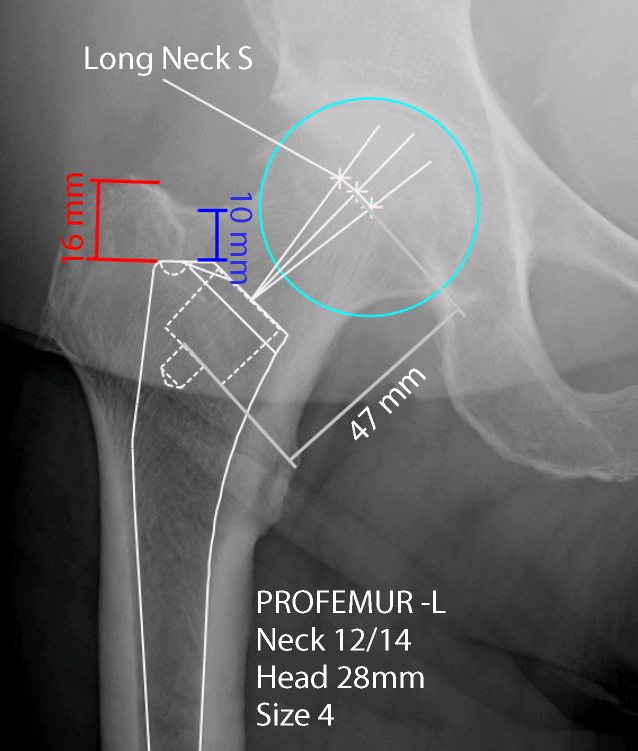

• measurement of the distance between the cranial anterior neck (blue) or of the trochanter (red) and the shoulder of the prosthesis (Fig. 1)

• Measurement of the distance between the depth of the broach pocket and the middle of the femoral head (grey) (Fig. 1)

Fig. 1

Digital planning preoperative. Cranial anterior neck distance (blue), trochanter distance (red), distance between the depth of the broach pocket and the middle of the femoral head (grey), the turquoise circle determines the center of the femoral head